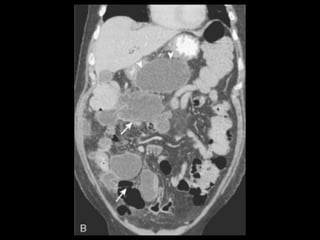

Pseudocistos

Coleções encapsuladas e uniloculadas de líquido

pancreático e material necrosado e proteináceo;

São necessárias 4 semanas ou mais para que um

pseudocisto evolua de uma coleção líquida aguda;

Mais comumente peripancreáticos, mas podem ser

observados no mediastino e na pelve;

Importância do contraste oral positivo;

Metade dos pseudocistos regride

Pseudocistos-TC

Coleção líquida redonda ou oval, com uma parede

fina ou espessa, que apresenta intensificação pelo

contraste;

RM: lesão uniloculada bem definida, hipointensa

em T1 e hiperintensa em T2;

Bolhas de gás: infecção, fístula ou à cistostomia

interna;

Hemorragia aguda dentro do cisto: hiperdensa

Estenose ou oclusão venosa, com formação de

varizes ou pseudoaneurismas.